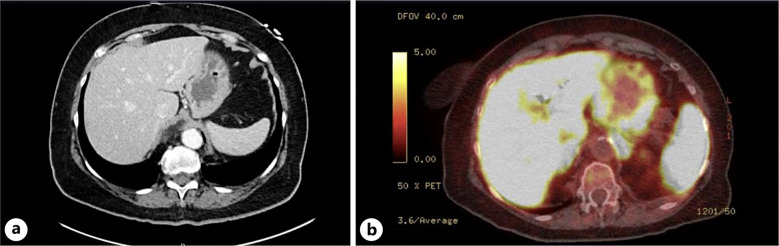

Case presentation: We report a case of ZES presenting duodenal perforation and later mimicking a hiatal hernia. This case highlights a complex presentation and underscores the importance of thorough evaluation, multidisciplinary management, and including rare diagnosis in the differential. Our patient presented to the hospital with nausea, back pain, and abdominal pain, and imaging demonstrated a perforated duodenum which was managed with surgical repair. Following surgery, the patient continued to have worsening nausea and acid reflux which was deemed to be due to a hiatal hernia noted on prior imaging until an esophagogastroduodenoscopy (EGD) was performed which confirmed the diagnosis of ZES.

Abstract Image